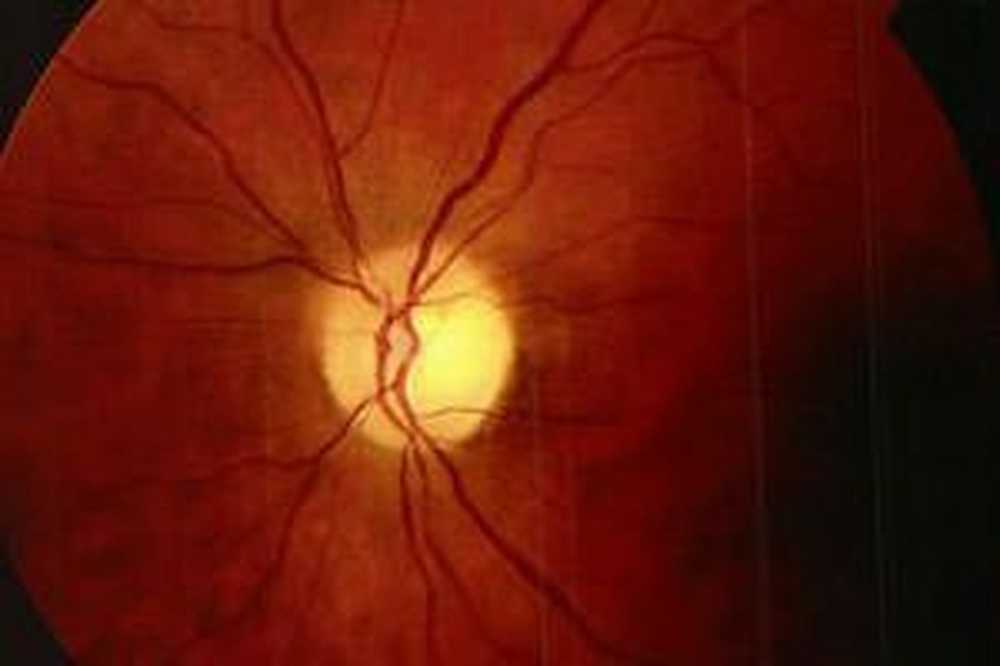

Атрофия зрительного нерва Лебера: Симптомы и лечение